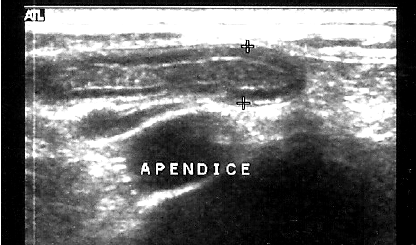

Na imagem da USG, vemos um apêndice vermiforme normal. A espessura máxima normal de um apêndice, em mm, é igual a: